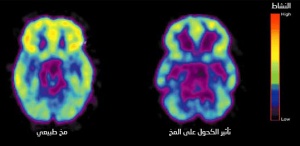

– الكحوليات لا تساعد على النسيان اطلاقاً. كل ما يحدث ان المخ يفقد القدرة على تسجيل الأحداث لفترة مؤقتة. و تحتاج خلايا المخ فقط الى 6 دقائق للاستجابة للكحول.

يقل نشاط المخ عند تناول الكحوليات (يمين الصورة) (المصدر: ScienceFocus)